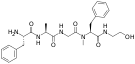

| Opioid peptides | Skeletal molecular images |

| Adrenorphin |  |

| Amidorphin |  |

| Casomorphin | |

| DADLE | |

| DAMGO |  |

| Dermorphin | |

| Endomorphin |  |

| Morphiceptin |  |

| Nociceptin |  |

| Octreotide |  |

| Opiorphin |  |

| TRIMU 5 |  |